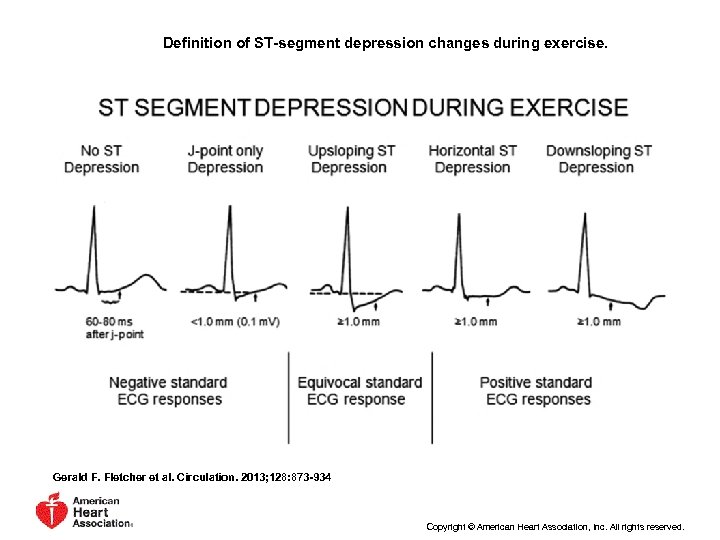

Относительные критерии прекращения нагрузки • Значимое снижение ST (горизонталь ное или AHA 2013 Exercise Standards for Testing and Training A Scientif Statement From the American Heart Association

Относительные критерии прекращения нагрузки • Значимое снижение ST (горизонталь ное или AHA 2013 Exercise Standards for Testing and Training A Scientif Statement From the American Heart Association

Definition of ST-segment depression changes during exercise. Gerald F. Fletcher et al. Circulation. 2013; 128: 873 -934 Copyright © American Heart Association, Inc. All rights reserved.

Definition of ST-segment depression changes during exercise. Gerald F. Fletcher et al. Circulation. 2013; 128: 873 -934 Copyright © American Heart Association, Inc. All rights reserved.